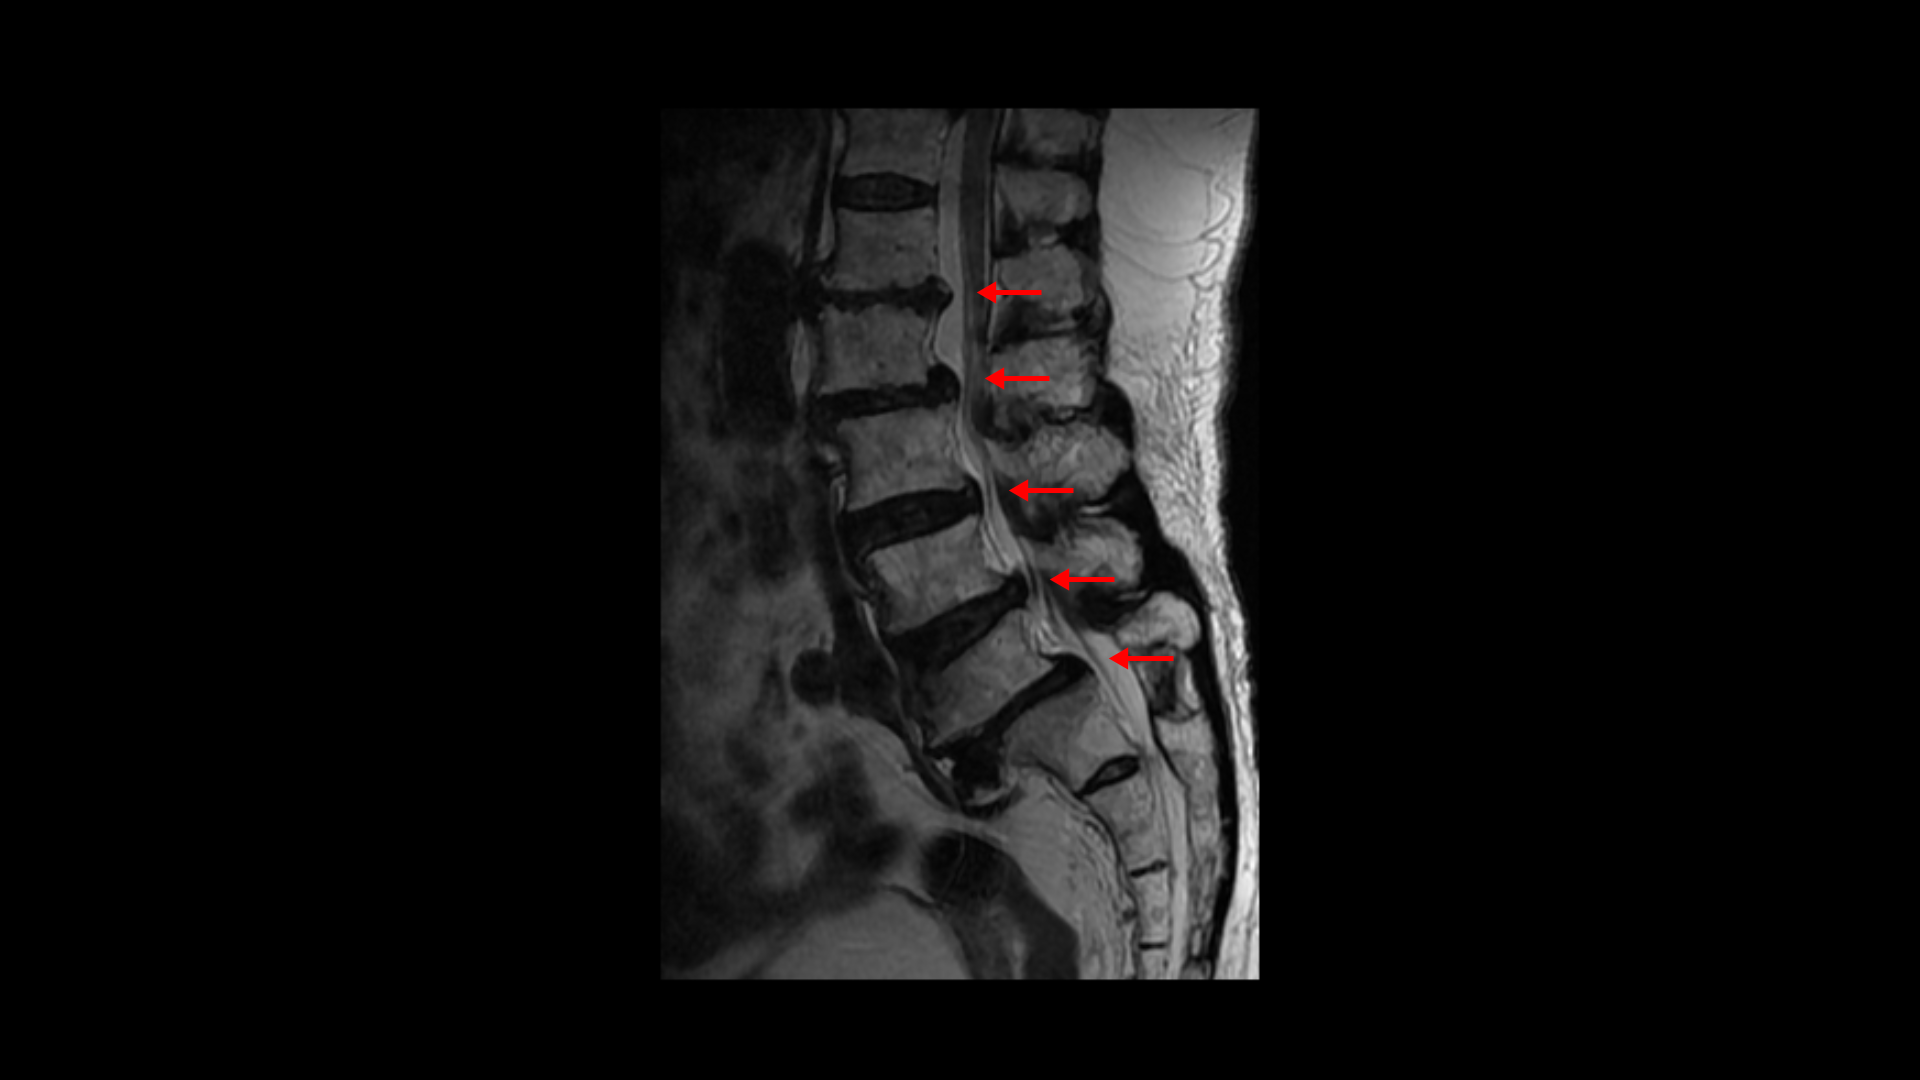

이분 MRI를 보면 보시다시피 허리의 5마디가 전부 퇴행이 진행되어 있습니다.

우선 전방전위가 2마디에 있고

여러 마디 2번 3번, 4번 5번에 척추관협착이 있고

2번 3번, 4번 5번, 오른쪽 신경가지가 빠져나가는 구멍들이 다섯 마디 전부가 다 오른쪽 좁아져 있습니다.

이분의 오른쪽 엉치와 다리가 저리고 아픈 원인은 이것 때문인 걸로 보입니다.